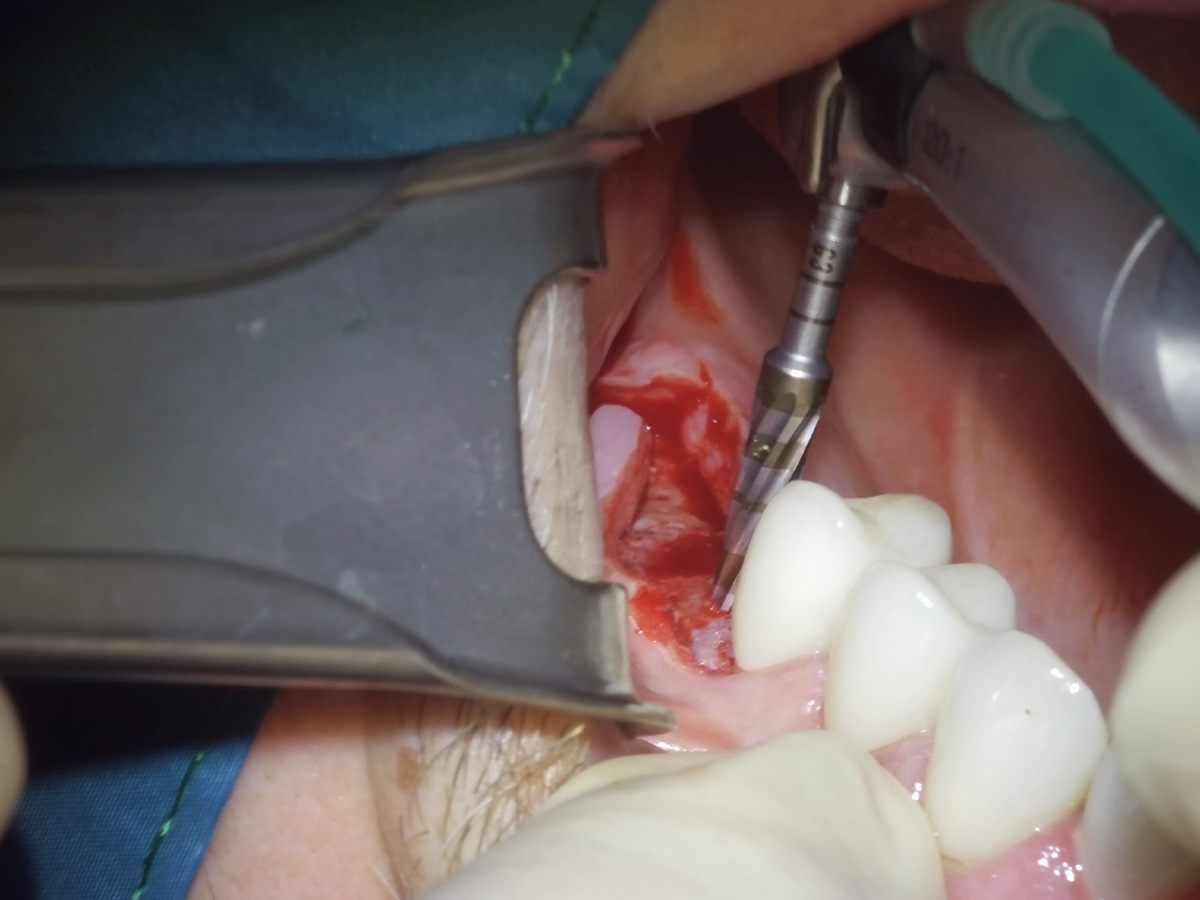

Abbildung 5

Implantatbettaufbereitung mit der Bone Condensing Methode (Versah Densah Burs).